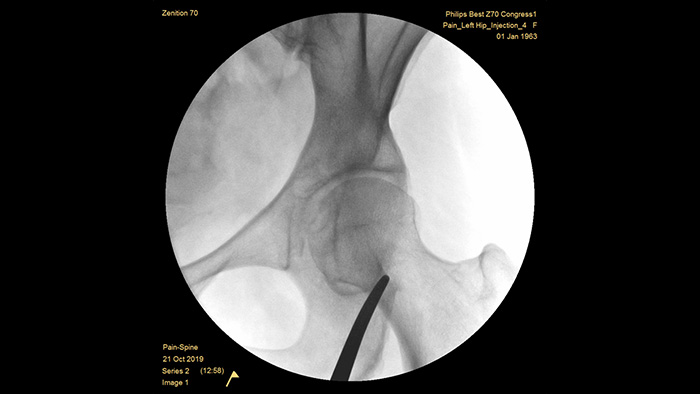

With our fourth generation Flat Detector systems, you gain exceptional image clarity of dense and complex anatomy. The compact form provides ample space and positioning ease for treating chronic pain in the joints. Our Position Memory2 increases first-time-right positioning to reduce scout images3 for efficient workflow in pain management cases. The Zenition 70 is available in three detector sizes: The FD 30 cm x 30 cm flat detector expands your view reducing procedure time and X-ray dose, the FD 26 cm x 26 cm offers broad anatomical coverage while the FD 21 cm x 21 cm provides ample space to work around patients.

The optimal depth of the fully counterbalanced C-arm provides ample room to position around obese patients and image the lumbar spine and hip. It supports over the table positioning, even with tables that have a large base.